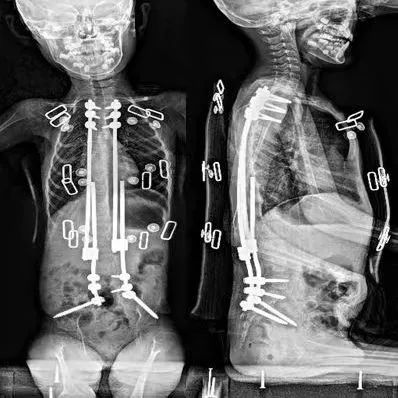

“在维洛的脊柱里安装一个可调节长度的金属支架,在干扰正常生长的情况下,达到矫正脊柱的目的。今后每年都要再做手术,延长生长棒的长度,直到生长发育完全停止后,再做最后一次融合术。”杨军林介绍,脊柱生长棒植入手术不仅可以矫正脊柱畸形,还可以通过增加胸廓高度,促进肺部生长并改善肺功能。手术后,维洛不但可以躺平、坐直,肺部功能也将大大得到提升,曾经因咳嗽吃不下饭的现象也将大为好转。

术前、术后CT图

术后的影像学检查提示:维洛的脊柱侧弯从69度变为了术后的10度。坐直以后的维洛身高高了很多,爸爸给他特制的电动轮椅以及家里各种护理用具都要“重新升级”,以适应维洛的新高度。